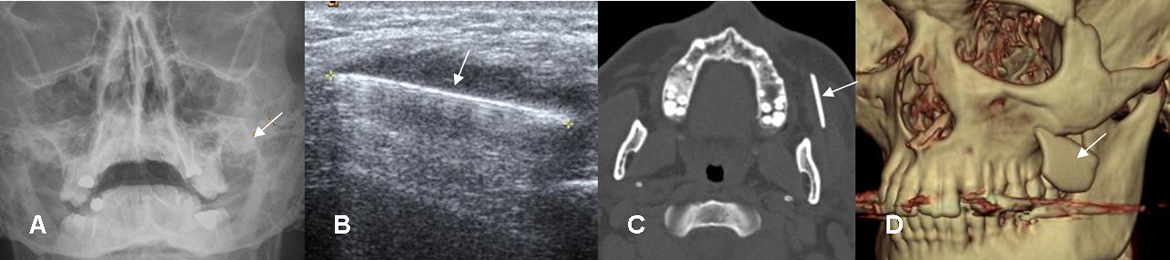

Fig 33. Cuerpo extraño. Paciente con antecedente de trauma abierto en la cara.

A: Rx AP. Imagen lineal y densa en la región malar izquierda.

B: Ecografía. Lesión ecogénica con hiper-refringencia posterior.

C: TAC axial y D: TAC reconstrucción en 3D. Imagen densa proyectada por debajo del hueso malar, que corresponde a cuerpo extraño. (Vidrio).